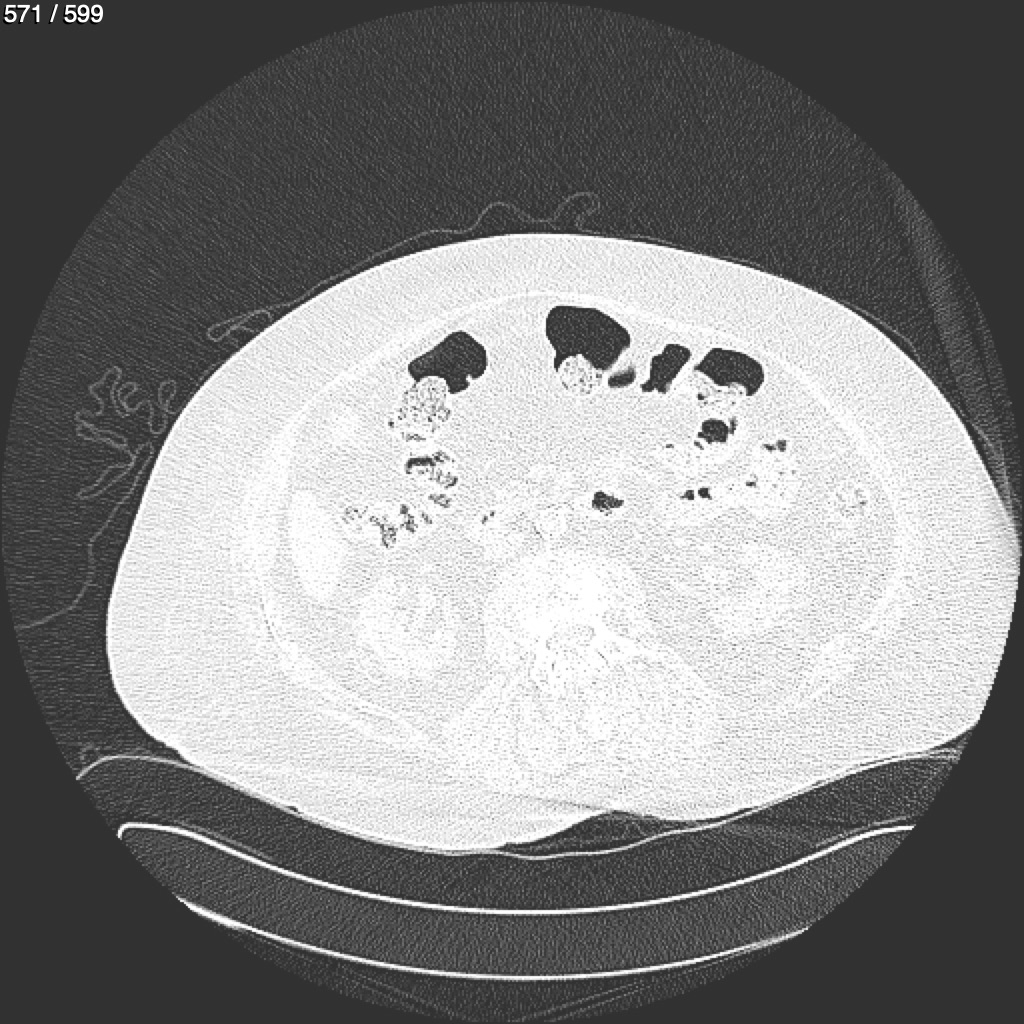

Home G​l​o​r​i​a​ ​G​l​a​d​y​s​ ​B​e​a​s​l​e​y​ ​-​ ​T​ó​r​a​x​ ​T​o​r​a​x​_​S​i​m​p​l​e​ ​(​A​d​u​l​t​o​)